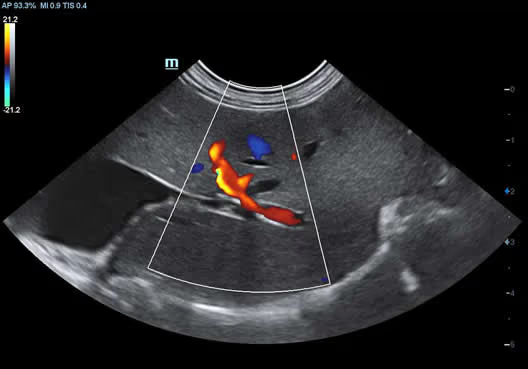

Köpek Böbreği

Köpek Böbreği

Hepatik Akış

Hepatik Akış